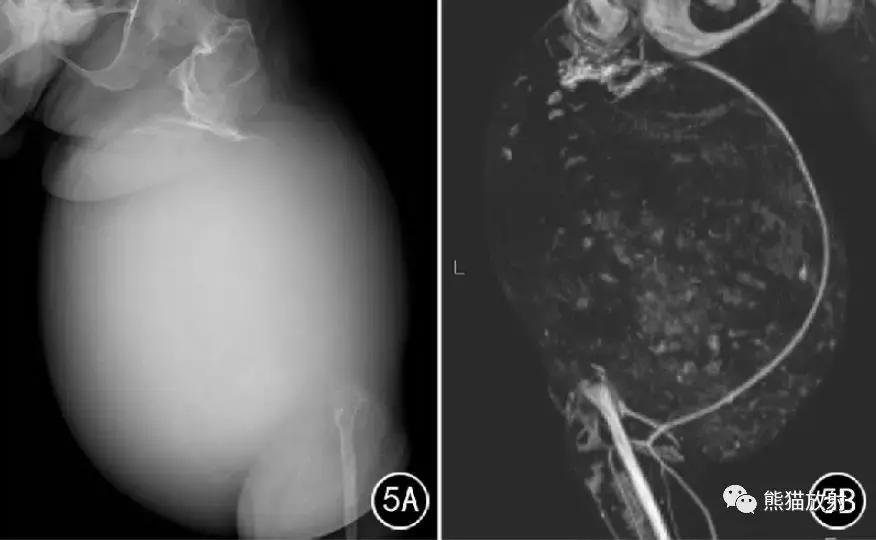

图5 男31岁。股骨中下段骨内型假肿瘤。DR示左侧股骨中下段骨质完全溶解吸收,股骨近端骨皮质呈“杯口状”,股骨粗隆间骨质囊状破坏,膝关节消失; 大腿软组织形成巨大肿块,其内有散在性斑点状高密影(A) ,CT血管造影显示股动脉受压推移(B)。